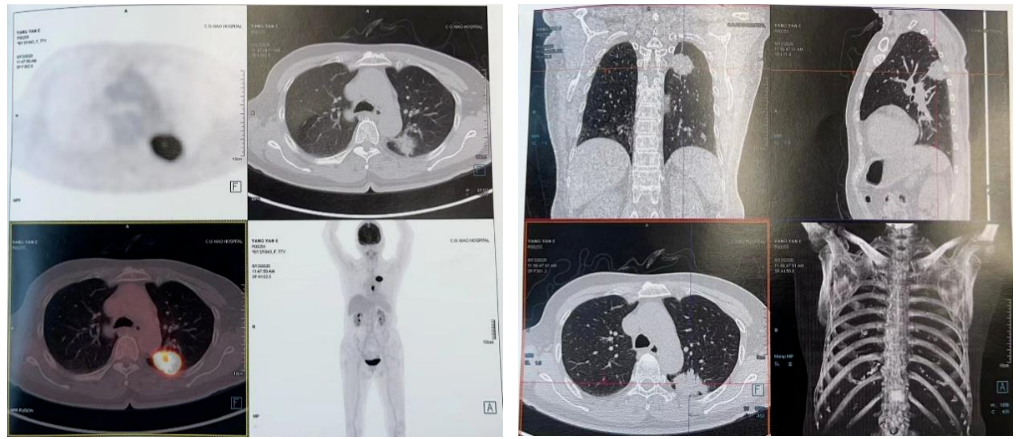

PET-CT(2020-08-13):食管胸下段管壁不均匀增厚,见放射性摄取增高,大小约18×14×27mm,SUVmax 14.6,符合食道癌表现。右侧肺门及纵隔(4R、5、7区)可见多个稍肿大淋巴结,最大约8×5mm,考虑炎性淋巴结可能性大。

左肺上叶尖后段团块状密度增高影,PET见放射性摄取增高,大小约40×29×31mm,SUVmax 28.0。病灶跨越左侧斜裂胸膜生长,密度均匀。左肺上叶胸膜下可见多发微小结节状密度增高影。建议治疗后复查,必要时活检排外恶性肿瘤的可能。

2021-10-28外院PET-CT:原食管胸下段管壁高代谢灶较前缩小,放射性较前减低,现大小约15×17×17mm,SUVmax 3.1,考虑为治疗后改变。左肺上叶团块状高代谢灶较前缩小,放射性摄取较前减低,现大小约25×18mm,SUVmax 2.1,考虑为治疗后改变。